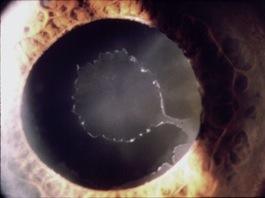

3. Glaucomi secondari. Si sviluppano come complicanza di altre condizioni mediche, quali interventi chirurgici, infiammazioni dell’occhio (uveiti), uso prolungato di colliri contenenti cortisone, traumi, ecc, e sono sempre caratterizzati da un aumento della pressione intraoculare. Una forma relativamente comune è il glaucoma associato alla pseudoesfoliatio capsulae, patologia caratterizzata dall’accumulo di materiale biancastro all’interno dell’occhio con conseguente ostacolo al deflusso dell’umore acqueo (foto in basso a sinistra). Meno frequente è il glaucoma pigmentario, in cui l’ostacolo al deflusso dell’umore acqueo è rappresentato da pigmento proveniente dalla superficie posteriore dell’iride (foto in basso a destra).

A sinistra: pseudoesfoliatio capsulae. A destra: glaucoma pigmentario (con la retroilluminazione si osservano i difetti dell’iride, che appaiono arancioni).